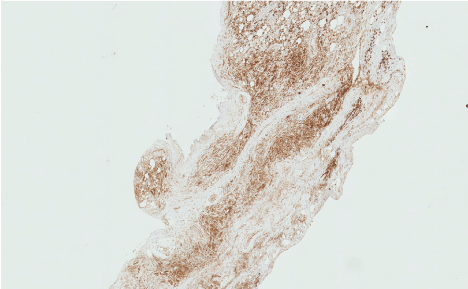

Figure 4: Histology showing diffuse staining with IgG4 positive cells [black arrow].